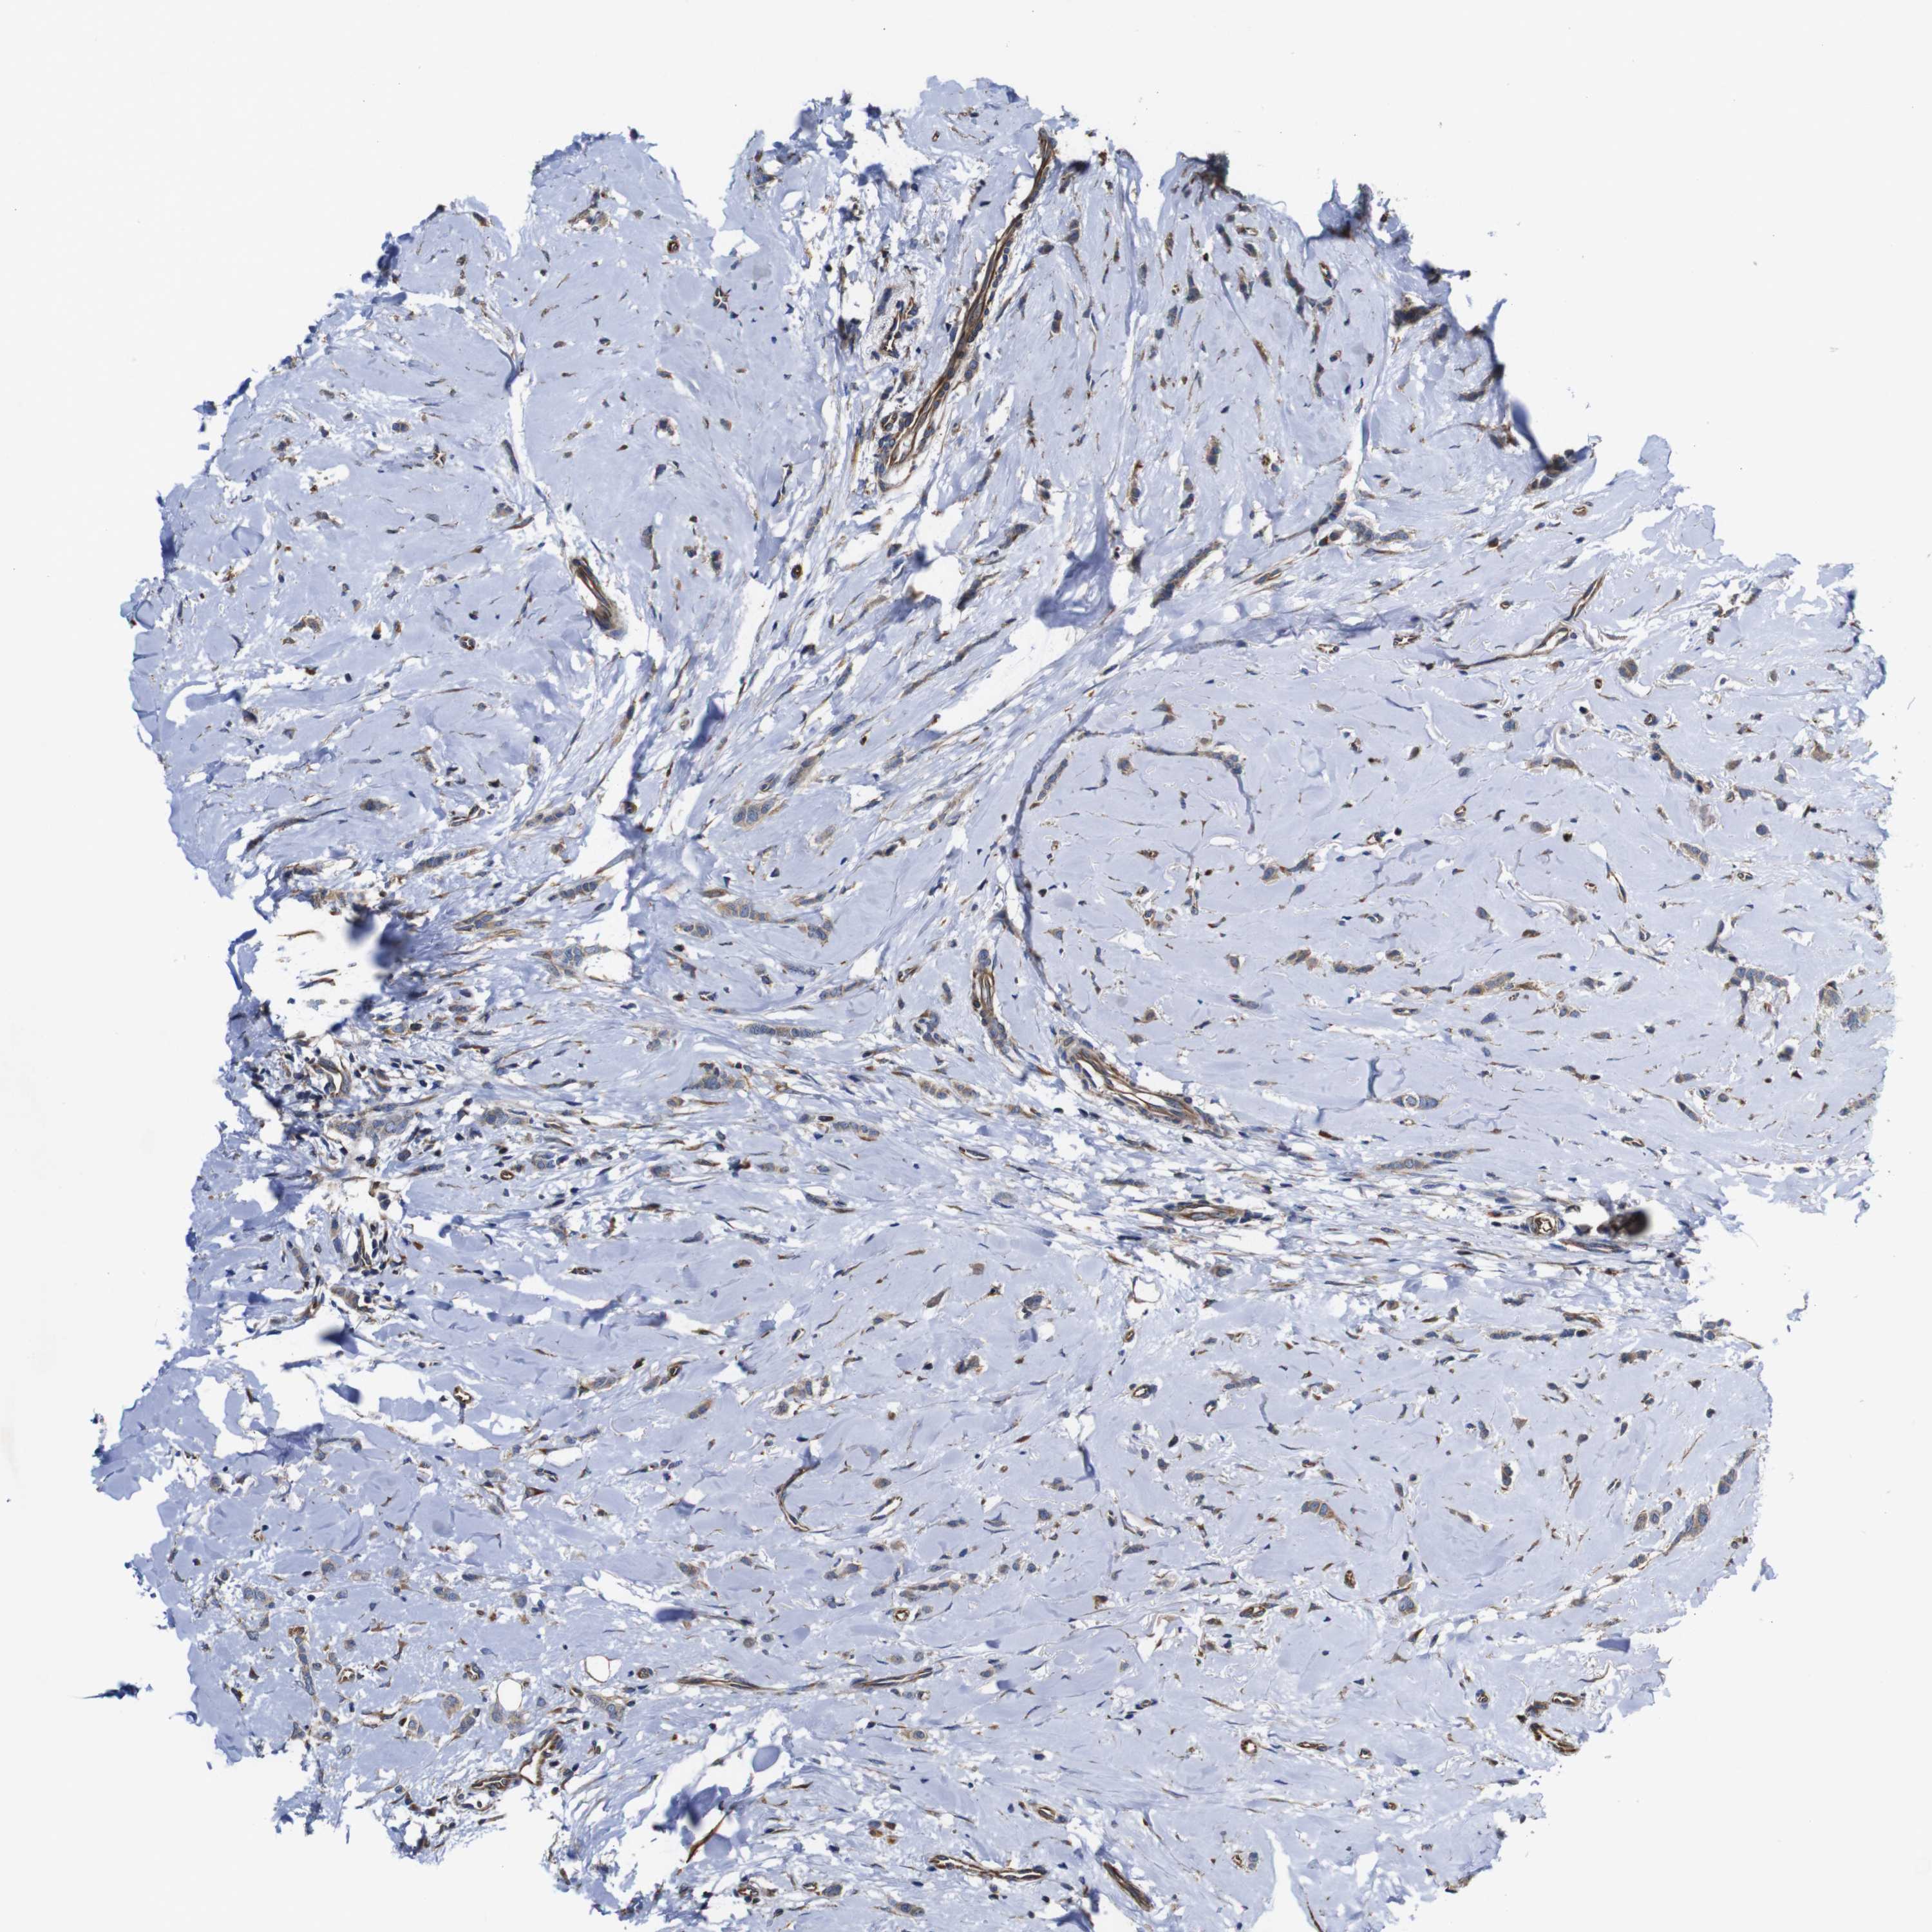

CANCER BREAST CANCER Show tissue menu

BRCA TCGA BRCA VALIDATION PROTEIN EXPRESSION